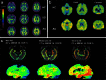

Aggregated tau protein is a major neuropathological substrate central to the pathophysiology of neurodegenerative diseases such as Alzheimer's disease (AD), frontotemporal dementia, progressive supranuclear palsy, corticobasal degeneration and chronic traumatic encephalopathy. In AD, it has been shown that the density of hyperphosphorylated tau tangles correlates closely with neuronal dysfunction and cell death, unlike β-amyloid. Until now, diagnostic and pathologic information about tau deposition has only been available from invasive techniques such as brain biopsy or autopsy. The recent development of selective in-vivo tau PET imaging ligands including [(18)F]THK523, [(18)F]THK5117, [(18)F]THK5105 and [(18)F]THK5351, [(18)F]AV1451(T807) and [(11)C]PBB3 has provided information about the role of tau in the early phases of neurodegenerative diseases, and provided support for diagnosis, prognosis, and imaging biomarkers to track disease progression. Moreover, the spatial and longitudinal relationship of tau distribution compared with β - amyloid and other pathologies in these diseases can be mapped. In this review, we discuss the role of aggregated tau in tauopathies, the challenges posed in developing selective tau ligands as biomarkers, the state of development in tau tracers, and the new clinical information that has been uncovered, as well as the opportunities for improving diagnosis and designing clinical trials in the future.